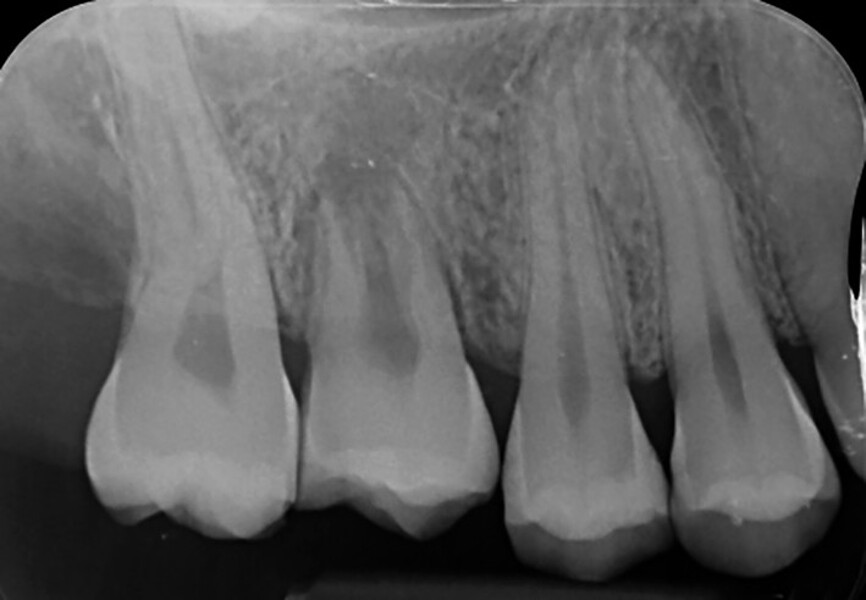

Fig. 18a: Radiographs: Pre-op panoramic.

Fig. 18b: Radiographs: Immediately after transplantation.

Fig. 18c: Radiographs: One-month recall, after endodontic treatment.

Fig. 18d: Radiographs: Eight-year recall.